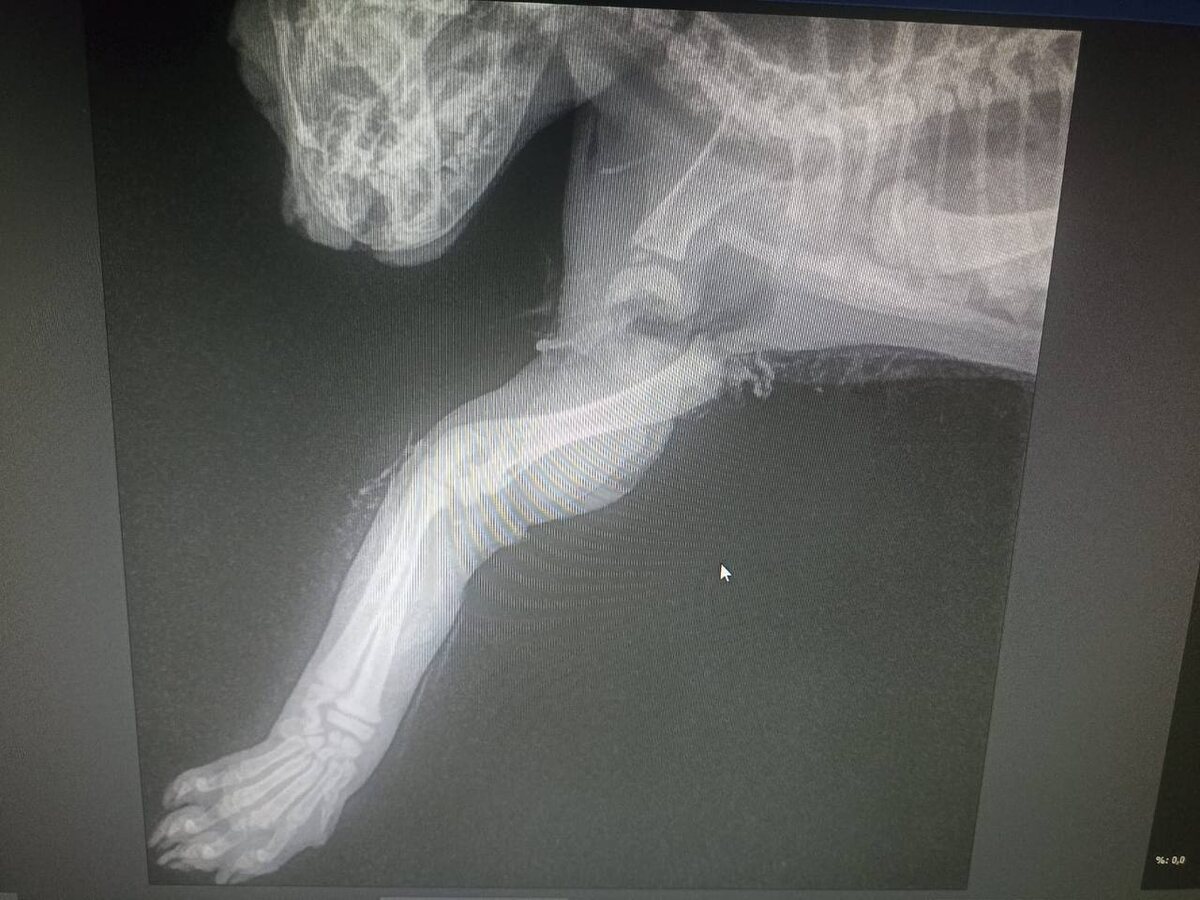

Приехал под капотом 🚘 автомобиля, лапка попала под ремень грм, который даже из за этого слетел и машина встала!

🆘Лапку просто вырвало , висит на коже(судя по снимку)

Завтра операция, так же котенок потерял кровь и будет переливание крови(донора ищем)